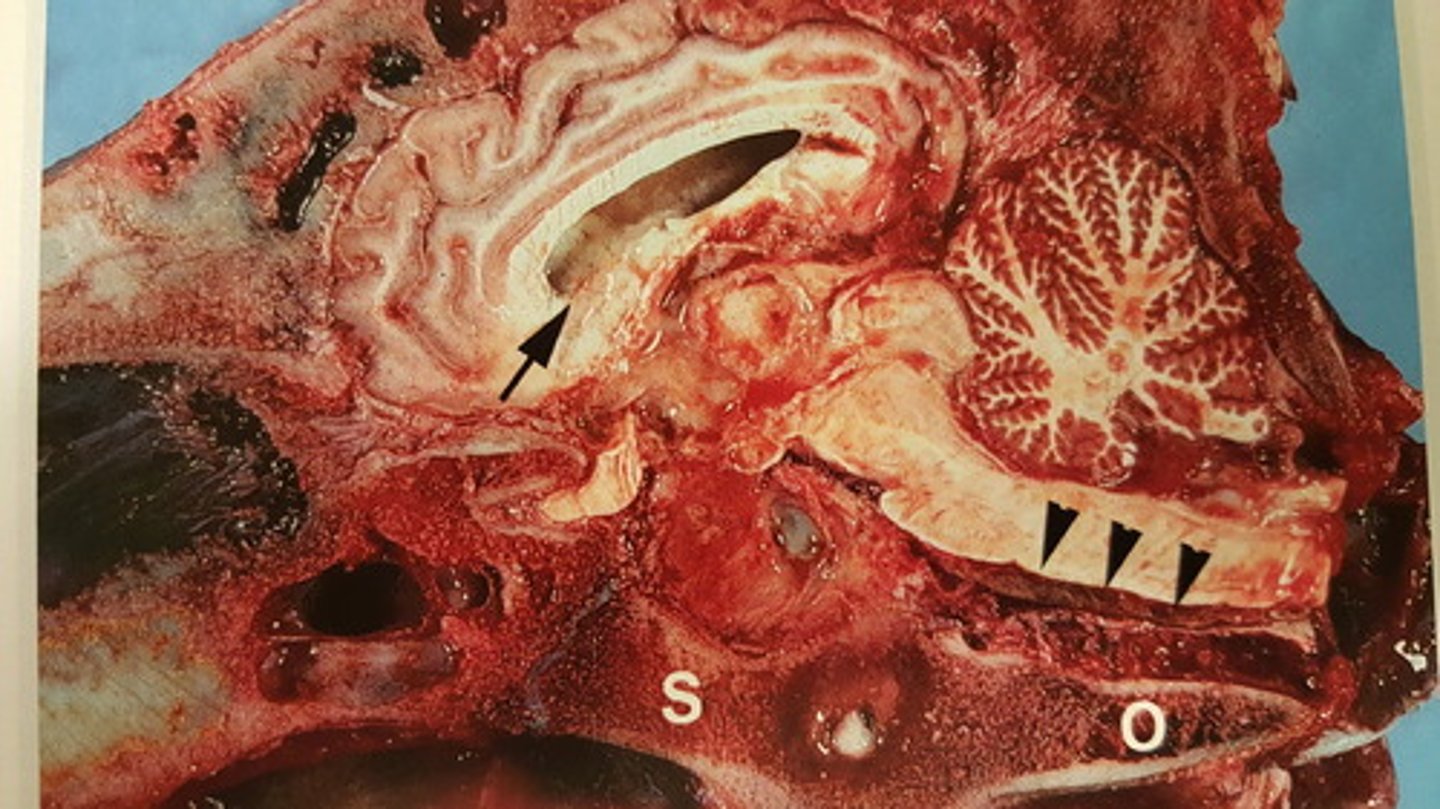

kronisk, fokal apostematøs osteomyelitis mellem S og O med opbrud til hypofysen. Kronisk meningitis (pil hovede). Purulent encephalitis og pyocephali (pil)

Hoved fra okse. Patoanatomisk diagnose?